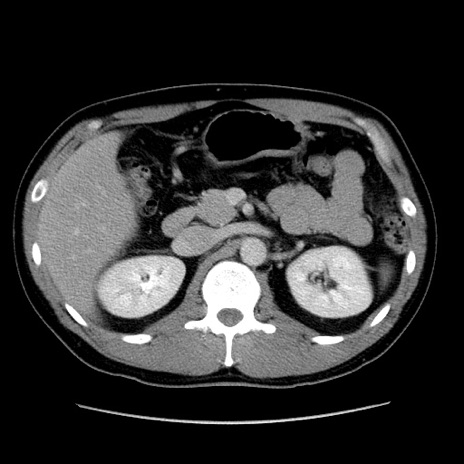

症例4(横断像)

【症例】30歳代男性

【主訴】腹痛、嘔吐

【現病歴】昨晩から突然の腹痛あり、その後嘔吐、軟便も出現。腹痛が改善しないため救急搬送となる。2日前にしめ鯖の食事歴あり。

【身体所見】意識清明、苦悶様、BP 135/90mmHg、BT 35.7℃、腹部:平坦、やや硬、心窩部〜臍部に自発痛、圧痛あり、筋性防御+、反跳痛-

【データ】WBC 8100、CRP 0.57